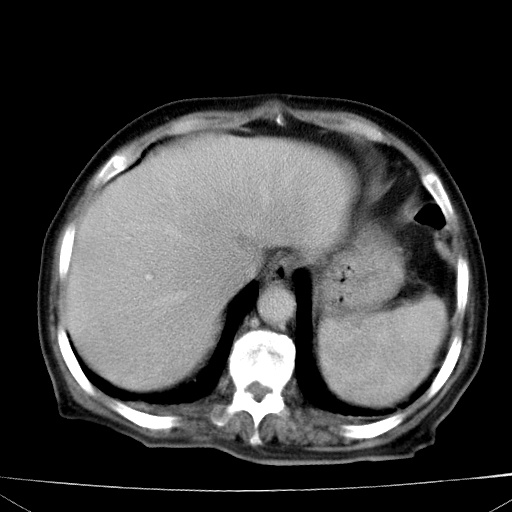

网站人气太旺!昨天的帖子就沉到海底,只好再发贴!ct18338:女 78岁,肝胆病变,已增强,再会诊!原帖链接:http://www.radida.com/bbs/forum.php?mod=viewthread&tid=50032

1)考虑胆囊癌侵犯肝脏并肝门区、腹膜后及右侧膈角后淋巴结转移。2)肝左叶近肝顶部囊肿。3)肝左叶肝内胆管结石。4)左肾近下极囊肿。

1、胆囊癌侵犯肝脏并腹腔及腹膜后淋巴结转移。

2、肝左叶外侧段囊肿。